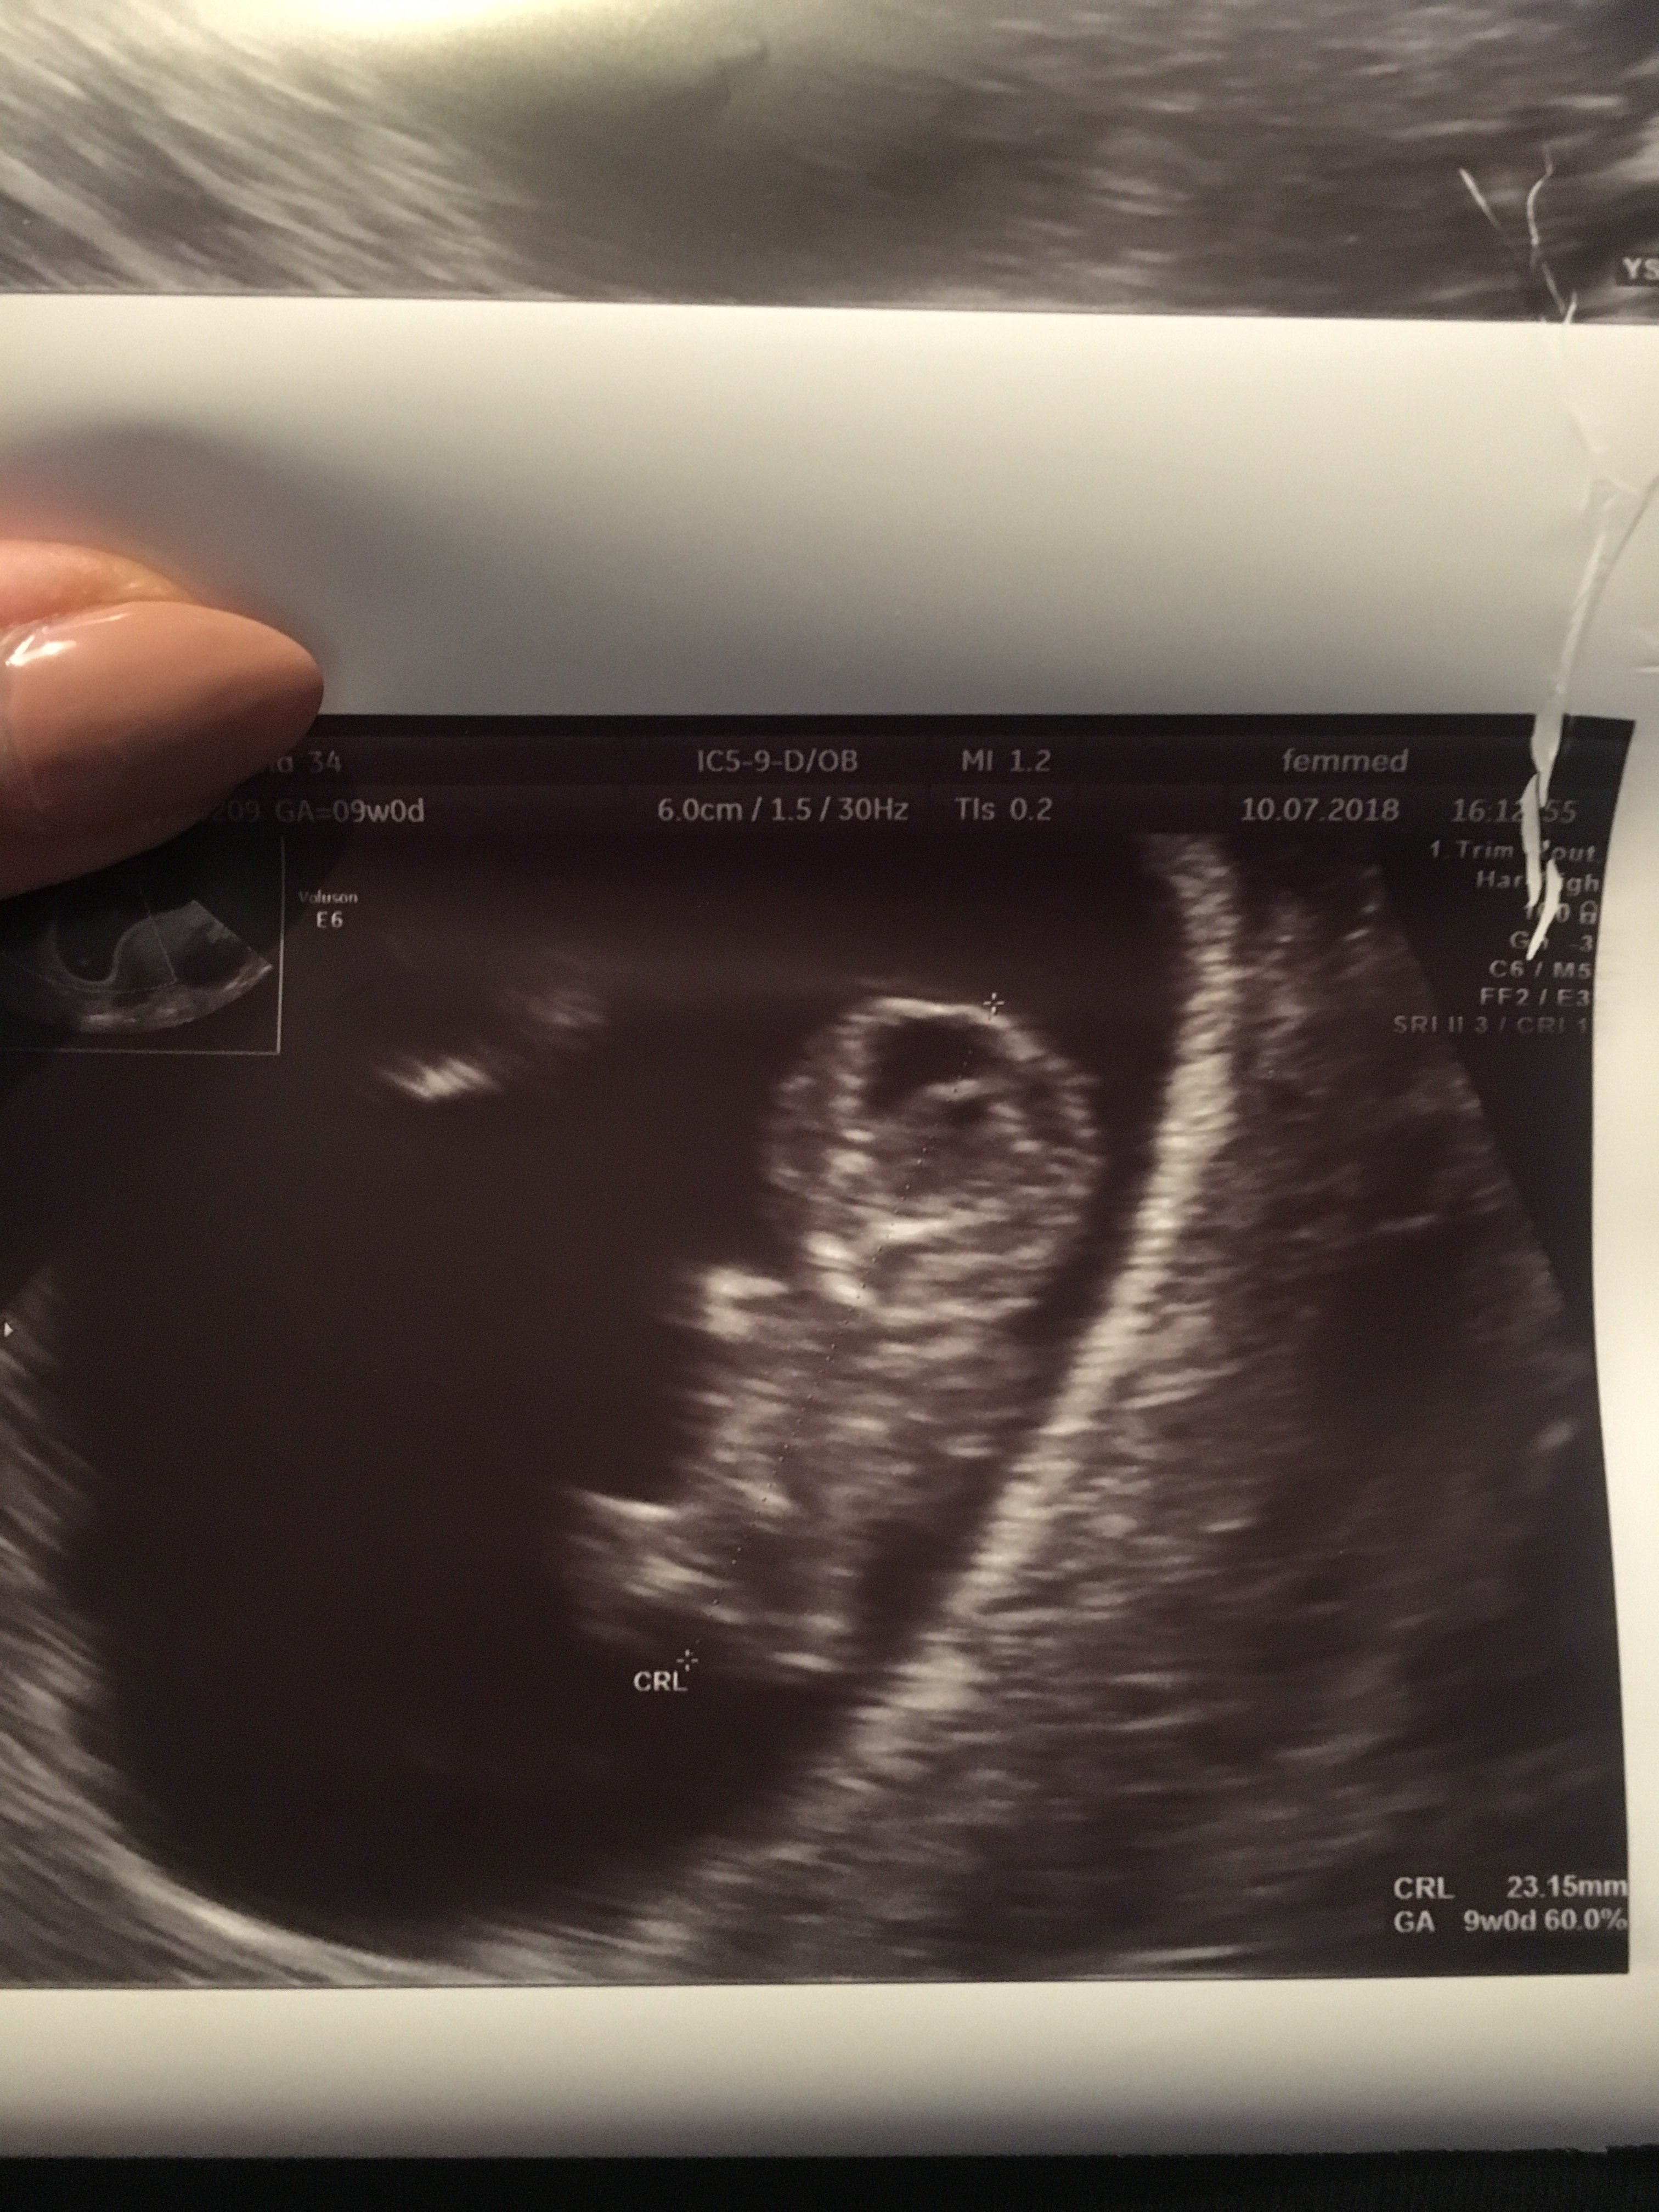

A ja już po wizycie. Bylismy razem. Mój A. pierwszy raz [emoji846] słyszeliśmy serduszko, mały do nas machał rączkami i to dość długo. Gin włączył nam na chwile serduszko na głos [emoji846] niesamowite to wszystko było [emoji846] maleństwo ma 23,15 mm, serduszko bije 167/ minutę. Na chwile obecna wszystko jest ok. Jutro mam tylko zrobić dodatkowo awidność na toxoplazme i różyczkę . 31.07 mam prenatalne usg, a po 24 mam zrobić hcg+PAPPA, koszt to 350 zł. Jak przeżyje prenatalne i wynik będzie ok to odetchne z ulga.

A to nasze maleństwo